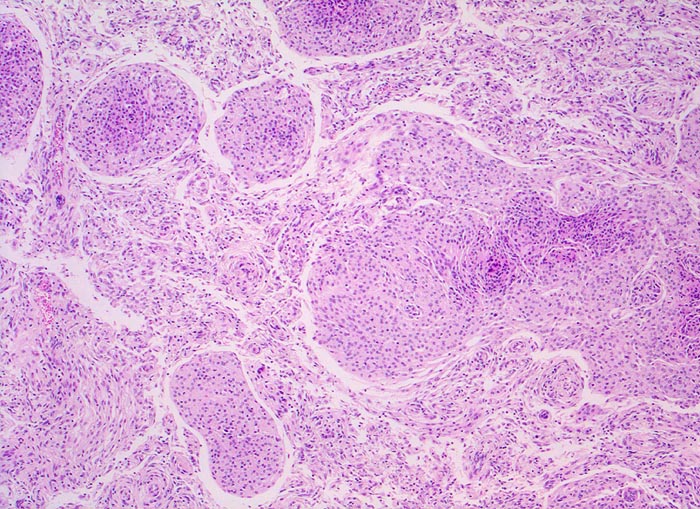

PathoPic – image database / PathoPic ID 5194 - meningotheliales Meningeom (WHO I)

meningotheliales Meningeom (WHO I)

Klassisches Meningeom bestehend aus teils kugeligen Verbänden monomorpher Tumorzellen. Zwischen den Tumorzellverbänden kleine Gefässe und schmale Bindegewebssepten.

Wegen erstmalig aufgetretenem epileptischem Anfall wird ein Schädel CT durchgeführt. Dabei kommt über der rechten Grosshirnkonvexität ein 3cm grosser runder Tumor zur Darstellung. Der Patient litt ausserdem seit mehreren Wochen über rechtsseitig lokalisierte Kopfschmerzen.

Histologie

50